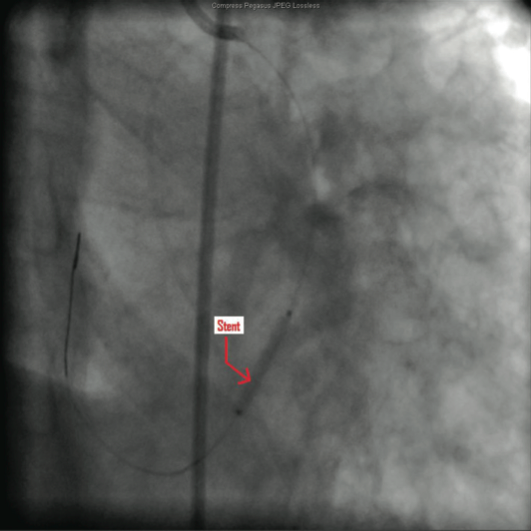

The catheterization and angiogram showed a patent left main coronary artery that bifurcated into the left anterior descending (LAD) and the left circumflex (LCX). The LAD had a mid 50% stenosis and the LCX was a large-sized vessel that gave off three obtuse marginal (OM) branches and continued distally into the right

side of the heart, filling the right coronary artery (RCA) from the distal end retrograde. The LCX had a mid 70-80% lesion that was confirmed by intravascular ultrasound (IVUS). The right coronary artery had no ostium and received retrograde filling via the LCX, continuing distally into the right myocardium. The LCX 80% mid stenosis was successfully revascularized with deployment of two drug-eluting stents. The patient was placed on post-procedure clopidogrel, simvastatin, beta blockers, and nitroglycerin.